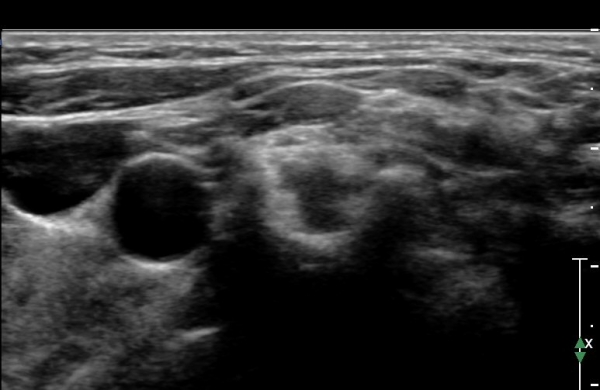

ŽÃËÀÚ¸¦ Á¶±Ý ¸»´ÜÀ¸·Î À̵¿ÇÏ¿© Àü»ç°¢±Ù°ú Á߻簢±Ù »çÀÌ¿¡¼­ »ó¿Ï½Å°æÃÑÀÇ Àú¿¡ÄÚ ºÎÁ¾ÀÌ °üÂûµÊ                  (»çÁø 2, 3).